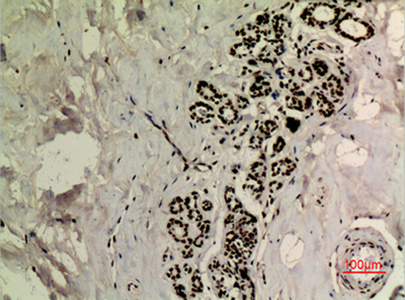

WB,IHC-P,IF-P,IF-F,ICC/IF,ELISA

WB 1:500-1:2000, IHC-P 1:100-300, ELISA 1:20000, IF-P/IF-F/ICC/IF 1:50-200